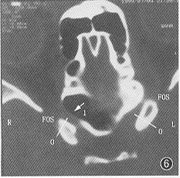

图4 右侧视神经管从蝶上筛窦内穿行,为管周型后筛,左侧视神经管向后筛内突入,形成视神经结节,双侧视神经管内侧壁均可见骨质缺损。

图5 右侧视神经管向蝶窦内明显突入形成视神经隆起,蝶窦部分包绕视神经管为Ш°。白箭头示向蝶骨小翼气化的蝶窦形成视神经上隐窝,黑箭头示视神经管内侧壁骨质缺损。

图6 右侧视神经管内侧壁毗邻蝶窦,其前段白箭头处可见8 mm长的骨质缺损。

400侧视神经管中,102侧可见内侧壁骨质缺损(图4~6),发生率为25.5%,其中右侧54例(27%),左侧48例(24%)。横断层面上的缺损长度为1.9~8.8 mm,平均(5.07±2.52) mm。视神经管内侧壁骨质缺损在各型筛、蝶窦中的发生率见表4。从表中可以看出,缺损在管周型筛窦的发生率为87.5 %(图4),明显高于其余4型;缺损在Ш度蝶窦的发生率为41.2%(图5),明显高于其余2型。